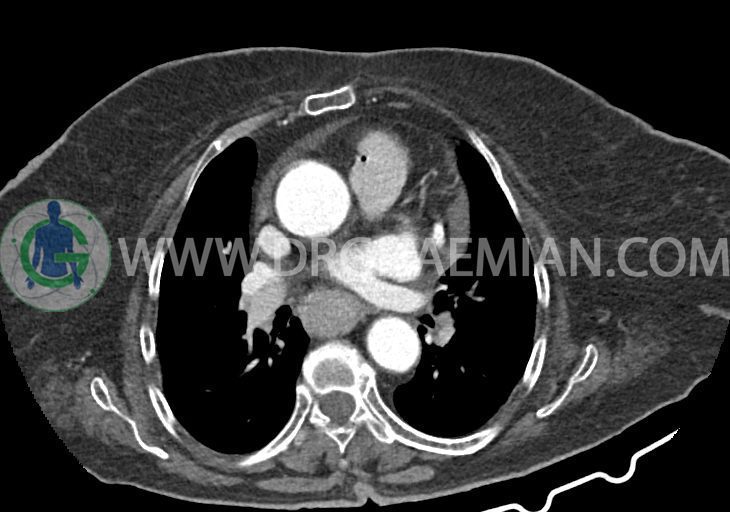

در سی تی اسکن اسپیرال ریه و مدیاستن – شکم و لگن با و بدون کنتراست خوراکی و وریدی (مولتی دیدکتور 16 با مقاطع ظریف و بازسازی های ساژیتال و کرونال):

–کاردیومگالی همراه با pericardial effusion خفیف

–یک ندول به ابعاد 19x18mm با حدود اسپیلوکه در سگمان لترال RML و دو ندول کوچکتر در مجاورت فوقانی آن به اقطار 6mm و 5mm ( مطرح کننده کارسینوم برونکوژنیک یا متاستاز )

–دیلاتاسیون نیمه فوقانی مری توراسیک ناشی از افزایش ضخامت circumferential توده مانند در یک سوم دیستال مری به طول 50mm ، که می تواند مطرح کننده انفیلتراسیون تومورال همراه با تنگی

–لنف نودهای non significant مدیاستینال با حداکثر SAD=6mm در فضای پره کارینا

–آئورت صعودی دیلاته به قطر 38mm